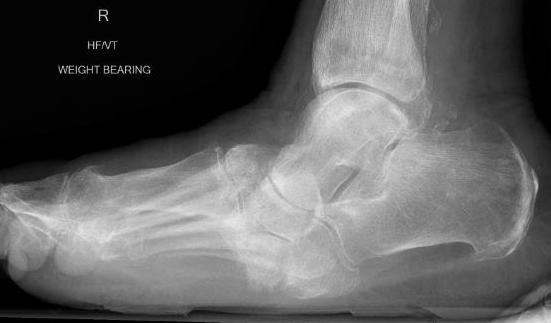

50% will get flat foot - subtalar OA - spring ligament attenuation - tibialis post dysfunction - progressive hind foot valgus |